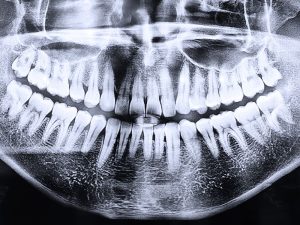

- Cambios en la boca: La forma de la boca puede cambiar con el tiempo debido a la reabsorción ósea, lo que puede afectar el ajuste de la prótesis.